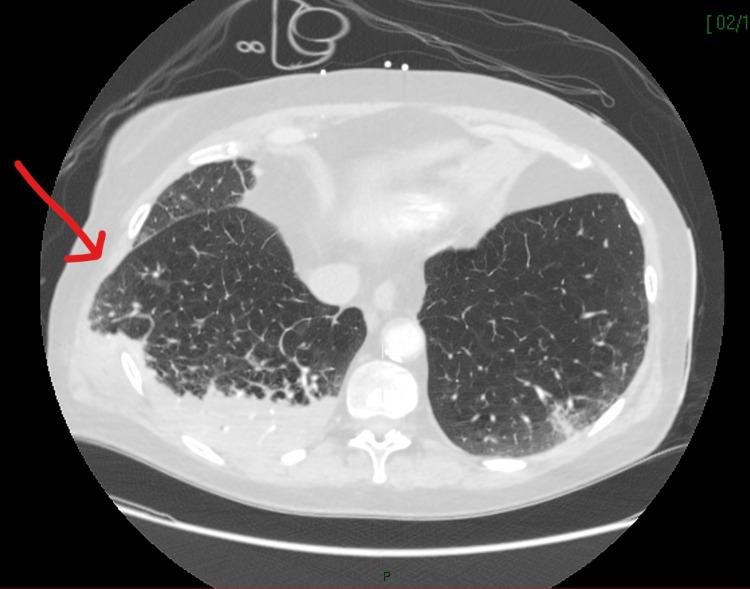

由于突然晕倒,患者接受了诊断性影像学检查:包括头部、胸部和腹部的CT,以排除肺栓塞和颅内出血导致的心脏骤停,以及确定败血症的来源。CT显示患者右下、中、上肺叶实变伴双基底不张,可能是败血症的病因。多重双侧前肋骨骨折,与心肺复苏术保持一致,右肺通过右胸壁突出(图1-2)。入院前一个月的高分辨率CT可用于比较,两份CT报告均显示持续广泛的肺气肿改变。

图2   胸部CT(轴位) 显示右侧肺疝和右下叶实变。红色箭头指向肺疝